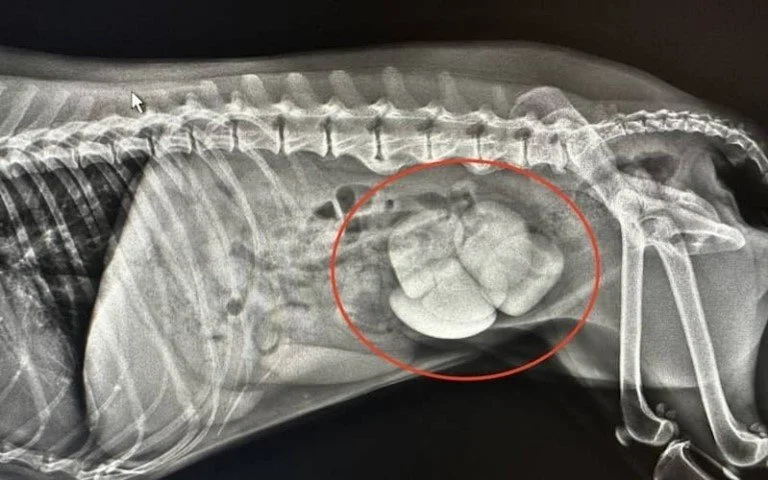

An x-ray showing a dog’s bladder that is filled with large struvite bladder stones present.

This diet can be used to prevent your dog having a cystotomy (surgery which involves incising into the bladder and removing the stones). The Hill's Urinary Prescription Diet c/d can dissolve struvite stones in dogs in 8–12 weeks. However, if your dog has lots of very large stones making them uncomfortable such as in the x-ray shown, we advise having the cystotomy surgery and then following the operation dependent on the stone identification to feed the Hills Canine Prescription Urinary Care c/d diet long-term to prevent future stone development. It is a balanced food that provides all the nutrition a dog needs.